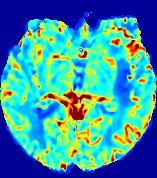

Slice #1Slice #2Slice #3Slice #4Slice #5Slice #6Dgtsuperscript𝐷gtD^{\text{gt}}Refer to captionRefer to captionRefer to captionRefer to captionRefer to captionRefer to caption(a)Refer to captionRefer to captionRefer to captionRefer to captionRefer to captionRefer to caption(b)Refer to captionRefer to captionRefer to captionRefer to captionRefer to captionRefer to caption(c)Refer to captionRefer to captionRefer to captionRefer to captionRefer to captionRefer to caption(d)Refer to captionRefer to captionRefer to captionRefer to captionRefer to captionRefer to caption(e)Refer to captionRefer to captionRefer to captionRefer to captionRefer to captionRefer to caption(f)Refer to captionRefer to captionRefer to captionRefer to captionRefer to captionRefer to captionRefer to caption000.060.060.060.120.120.120.180.180.180.240.240.240.300.300.30(mm2/s)𝑚superscript𝑚2𝑠(mm^{2}/s)

Figure 13: PIANO effectiveness and robustness testing: diffusion imaging via diffusion. Top row shows Dgtsuperscript𝐷gtD^{\text{gt}} used for simulating the ground truth pure diffusion. (a)-(f) refer to the results for D𝐷D estimated from the ground truth pure diffusion image time-series where Rician noise at levels 0%, 2%, 4%, 6%, 8%, 10% was added respectively.

Similarly, starting from the same initial condition C0superscript𝐶0C^{0} as in the ‘Advection Imaging’ experiment for each patient, we simulate concentration time-series {Cti(Ω)|i=0, 1,, 40}conditional-setsuperscript𝐶subscript𝑡𝑖Ω𝑖0140\{C^{t_{i}}\in\mathbb{R}(\Omega)|i=0,\,1,\,\ldots,\,40\} via a diffusion PDE, where we define the ground truth diffusivity D:=Dgtassign𝐷superscript𝐷gtD:=D^{\text{gt}} via the ADC map of the ISLES 2017 training set (ADC values are scaled by 0.000010.000010.00001 to ensure numerical stability):

Note this is likely not a spatially representative ground-truth for perfusion imaging, as it measures different effects from diffusion imaging. However, we still use it as a quasi-realistic pattern of diffusivity in the brain. We also added 2%, 4%, 6%, 8%, 10% levels of Rician noise to obtain simulations of ‘Diffusion Imaging’. The estimated Destsuperscript𝐷estD^{\text{est}} given concentrations of all noise levels for one patient are shown in Fig. 13, PIANO estimation results for all patients are summarized in Fig. 11 (b). Again, PIANO demonstrates its capability to recover the underlying diffusion field. In Fig. 13, when the noise level is increasing, some noisy patterns indeed appear in the associated Destsuperscript𝐷estD^{\text{est}}. Note that the ground truth diffusivity applied in this simulation experiment is about ten times larger than the diffusivity estimated in reality (Fig. 3, Fig. 4).